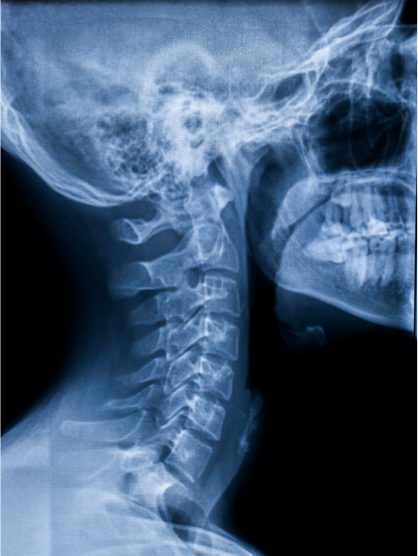

Originally described in the Japanese population, where it affects approximately 4-5% of the population, OPLL is seen in approximately 1.5% of the U.S. population. It most commonly becomes symptomatic in those 40-70 years of age, presenting as a progressive myelopathy. OPLL is more common in the cervical spine than either the thoracic or lumbar segments, although the entire spine may be involved. Presenting symptoms include progressive gait difficult, coordination problems of the hands associated with burning upper extremity pain, as well as upper extremity radicular pain, weakness and numbness. Diagnosis is based on MRI to determine the degree of cord compression as well as to identify the number of levels involved; CT of the cervical spine is indicated as well to confirm signal changes associated with the presence of the abnormal bone anterior to the cord as well as to determine the “occupation ratio.” (See below.)

Unfortunately, if presenting symptoms show myelopathic features, progression is common and operative decompression is indicated. The Occupation Ratio refers to a measure on CT of the anterior-posterior distance of the spinal canal occupied by the abnormal bone divided by the expected normal anterior-posterior distance of the canal at this level. An occupational ratio of 30-60% predicts the development of myelopathy, while a ratio of greater than 60% requires immediate surgical decompression in almost all patients healthy enough to tolerate the surgery.

The following case study illustrates the complexity of a patient with multi-level continuous cervical OPLL presenting with a progressively severe cervical myelopathy and a high occupation ratio requiring anterior-posterior surgery.